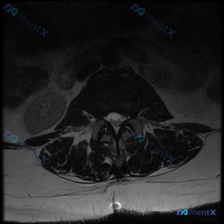

这是一张腰椎MRI的T2加权轴位图像,具体表现如下:

- 椎间盘:该节段椎间盘信号强度降低,提示椎间盘退变;椎间盘后缘可见局限性向后突出,形成向椎管内延伸的低信号影

- 椎管内容物:硬膜囊前方受压变形,由正常圆形/椭圆形变为受压变扁,突出物直接压迫硬膜囊前缘;脑脊液高信号下可见部分马尾神经根

- 小关节:双侧腰椎小关节增生肥大,关节间隙不清晰、信号减低,提示小关节退变

- 黄韧带:未见明显增厚或钙化

- 椎旁软组织:双侧肌肉形态对称,未见异常水肿或占位

- 椎管空间改变:侧隐窝因椎间盘突出+小关节增生出现空间受限,中央椎管存在程度不一的狭窄